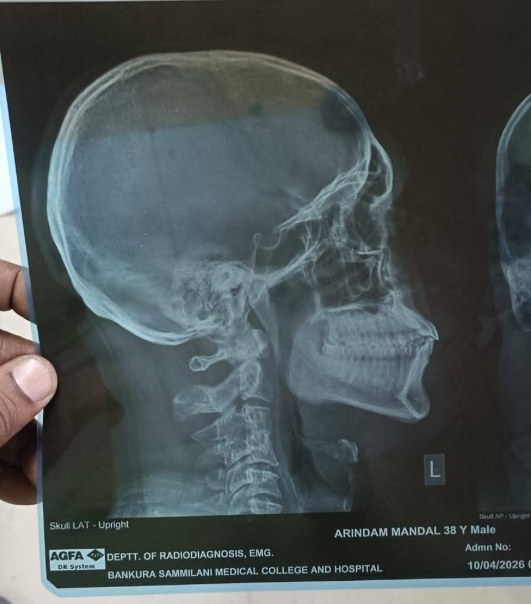

সংগঠনের অভিযোগ, তৃণমূলের ছাত্রনেতা সুরজ বক্সের নেতৃত্বে এই হামলা চালানো হয়েছে বলে অভিযোগ । যদিও এই অভিযোগ সম্পূর্ণভাবে অস্বীকার করেছে তৃণমূল।হামলায় অরিন্দম মণ্ডল গুরুতর জখম হন। তাঁর নাক ও মাথায় গভীর আঘাত লাগে এবং রক্তাক্ত অবস্থায় তাঁকে দ্রুত উদ্ধার করে বাঁকুড়া সম্মিলনী মেডিক্যাল কলেজে ভর্তি করা হয়।

চিকিৎসকরা তাঁর শারীরিক অবস্থার উপর নজর রাখছেন বলে জানা গেছে।এই ঘটনাকে কেন্দ্র করে জেলার রাজনৈতিক ও শিক্ষক মহলে তীব্র উত্তেজনা ছড়িয়েছে। সংগ্রামী যৌথ মঞ্চের পক্ষ থেকে দোষীদের দ্রুত গ্রেফতার ও কড়া শাস্তির দাবি তোলা হয়েছে। অন্যদিকে, রাজনৈতিক মহলে শুরু হয়েছে পাল্টা অভিযোগের পর্ব, যা ভোটের আবহে বাঁকুড়ার রাজনীতিকে আরও উত্তপ্ত করে তুলেছে।